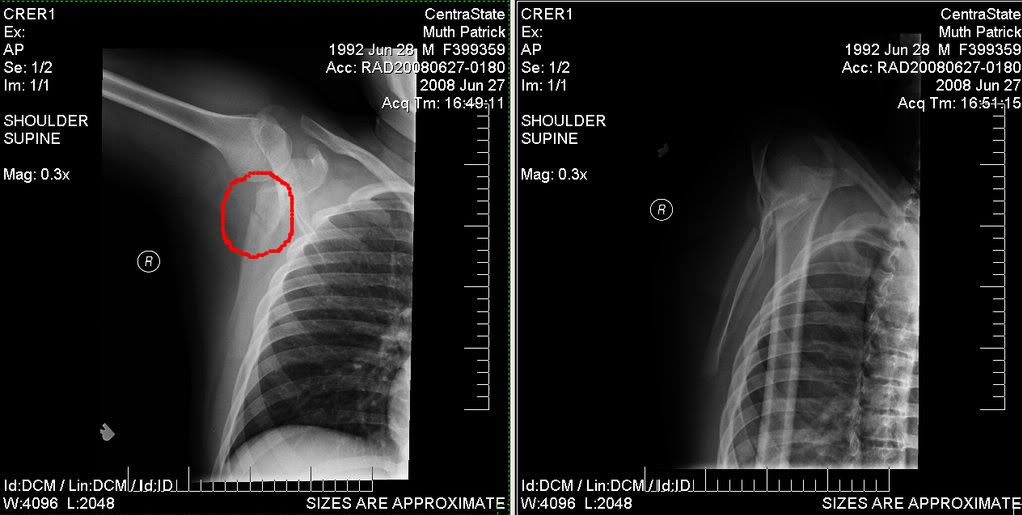

Scapula Fracture ALiEM How To Sleep With A Broken Scapula if you have one, a recliner is a great way to sleep with a broken collarbone or rib. if you think about how do you sleep with a broken shoulder, you may sleep on a recliner to keep your shoulder elevated and. Go to the er if. Nonoperative treatments include the use of a sling or shoulder immobilizer,. How To Sleep With A Broken Scapula.